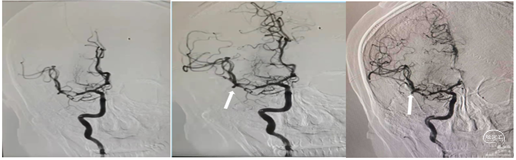

导引导管到位:右侧股动脉置8F动脉鞘,0.035泥鳅导丝携带单弯导管外衬8F导引导管到达右侧颈总动脉近分叉处。撤出单弯导管和泥鳅导丝。

裸奔抽吸:通过导引导管将中间导管0.070-125cm置于颈内动脉起始部,"裸奔"边抽吸边上,抽吸3次,到达C4段,但以远血管仍不通畅。

导丝导引下抽吸:微导丝携带微导管,在中间导管支撑下到达C6-M1起始部,中间导管再次边抽吸边上至M1起始部,抽出部分血栓,中间导管造影示大脑前通畅,大脑中动脉仍不通。

支架取栓联合抽吸:再次将微导丝偿试通过M1段,到达大脑中动脉分叉部分,跟进微导管至分叉部,通过微导管释放4ⅹ20mm取栓支架,静置5分钟,向前跟进微导管,收拢支架,跟进中间导管至M1。边抽拉微导管和支架负压抽吸下将支架拉入中间导管内撤出体外,抽出大量黯红色血栓,支架内抓出黯黑色血栓。

中间导管内造影示大脑中动脉上干、下干通畅,远端血流良好,但上干、下干分叉后血管内仍有发白,考虑仍有血栓或斑块。

再次取栓:再次将支架置于M2段上干,释放支架,跟进中间导管至M1分叉近端,再次取栓和抽吸,取出少量血栓。